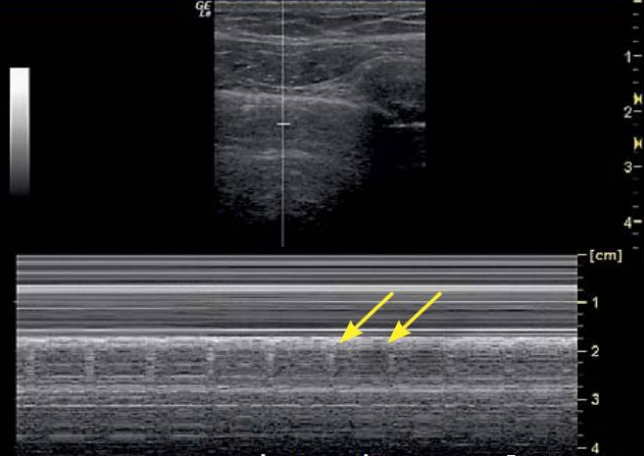

临床遇到上述情况,可以采用M模式(M-mode)进一步评估。正常情况下,肺超所见如沙滩一样,但如果出现条码征或平流层征(图7),考虑气胸可能。另一个在气胸患者中发现的特有征象为”肺点“(图8)。肺点是脏层胸膜与壁层胸膜的分离处,即气胸的边缘。在肺点的一侧是肺组织与壁层胸膜相接触,而其他部分在此处开始出现脏层、壁层胸膜的分离。如果在前胸壁出现胸膜滑动征消失、A线,并发现有肺点,则诊断气胸的特异性高达100%。临床中很多患者处于平卧位或半卧位,气体基本分布于前胸,靠近前胸壁的一侧基本看不到胸膜滑动。如果是小范围气胸,或肺并未被完全压缩,找到肺点的可能性较大。虽然肺点被当做超声诊断气胸的金标准,但没有发现肺点也不能排除气胸,例如在大面积气胸甚至整个肺组织被压缩的情况下,无法找到肺点,但整个肺野可能会表现为没有胸膜滑动的A线。同时,在临床中如遇到巨大肺大泡患者,当出现呼吸很窘迫时,也可能会观察到肺点。因此,临床中诊治疾病尤其是气胸时,超声仅为辅助诊断工具,仍需结合患者的临床表现等具体情况,进行综合观察及评估。